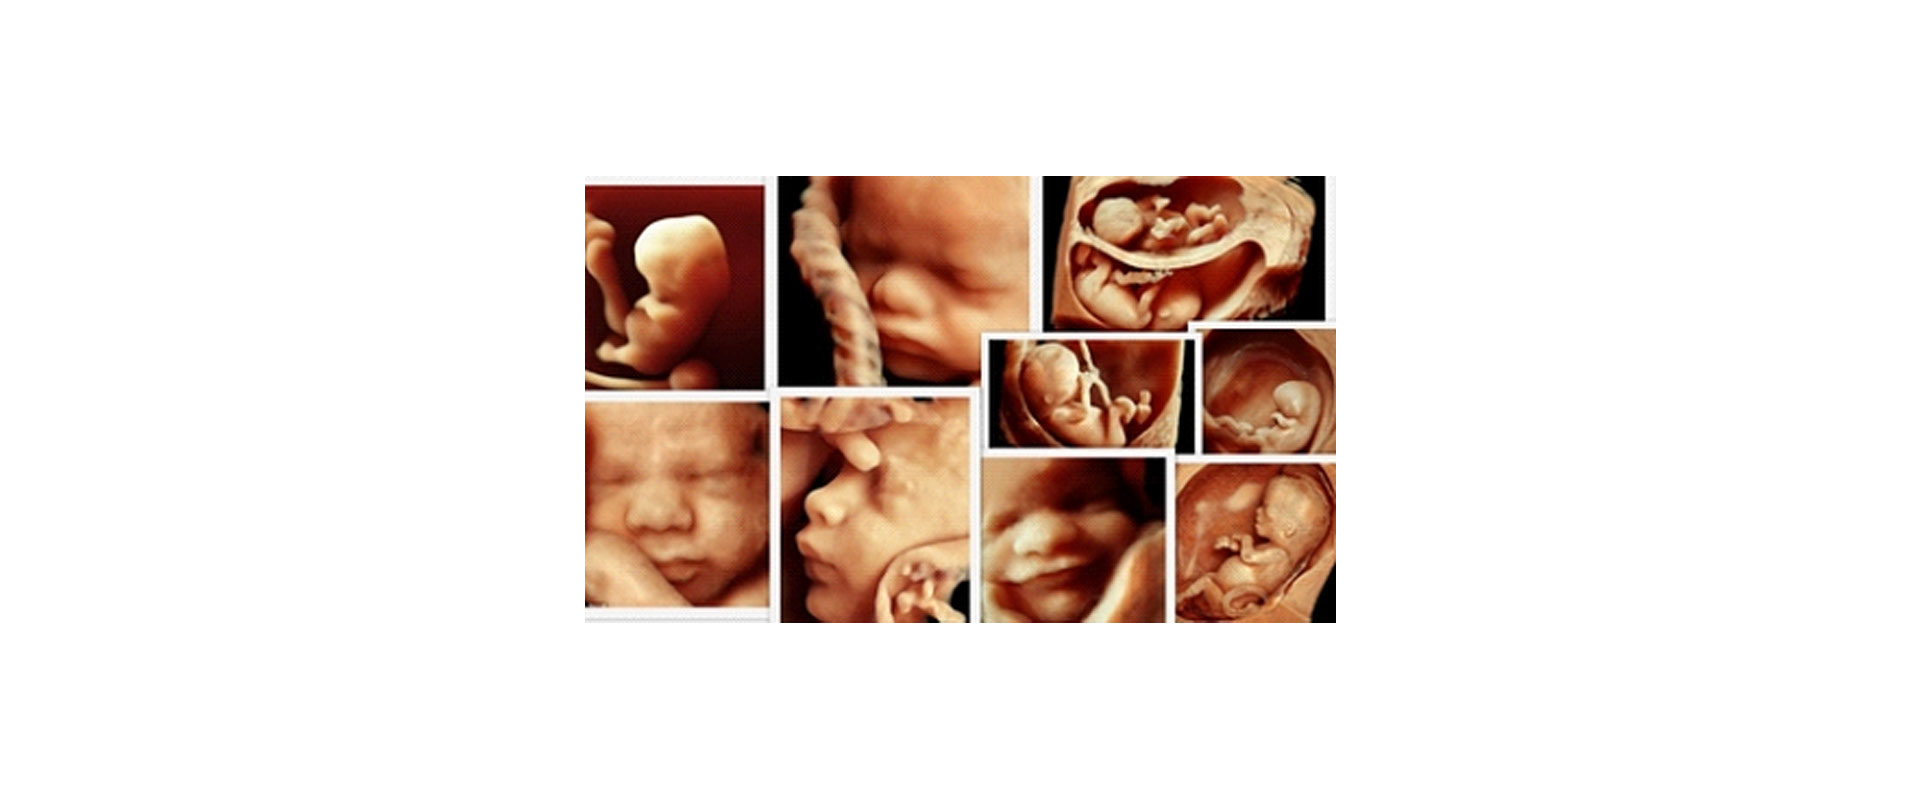

⦁ πιο «πραγματικές» εικόνες του εμβρύου στο φυσικό του περιβάλλον

✓ Παρακολούθηση Εγκυμοσύνης: Λεπτομερείς εικόνες του εμβρύου για την αξιολόγηση της ανάπτυξης και της υγείας του και συμπληρωματική ανίχνευση ανωμαλιών σε συνδιασμό με το 2D υπερηχογράφημα.

Η συνηθισμένη δισδιάστατη 2D υπερηχογραφική εικόνα μας δίνει τις πιο σημαντικές πληροφορίες για το έμβρυο. Σε κάποιες σπάνιες ανωμαλίες το τρισδιάστατο υπερηχογράφημα μπορεί να μας βοηθήσει να δούμε καλύτερα ορισμένα όργανα, ωστόσο είναι το δισδιάστατο υπερηχογράφημα που βασικά θα μας κατευθύνει στη διάγνωσή μας. Έτσι, πιθανόν και να αυξάνεται η ακρίβεια της διάγνωσης, και παράλληλα, γίνεται πιο κατανοητή και από τους γονείς.

⦁ Ένα υπερηχογράφημα 3D/ 4D μπορεί να πραγματοποιηθεί οποιαδήποτε στιγμή της εγκυμοσύνης αρκεί η θέση του μωρού να είναι ευνοϊκή. Είναι σύνηθες να εκτελείται μεταξύ 20ης – 34ης εβδομάδας της κύησης. Τα καλύτερα αποτελέσματα λαμβάνονται αν το υπερηχογράφημα πραγματοποιηθεί μεταξύ 27ης – 32ης εβδομάδας γιατί τότε η αναλογία διαστάσεων του μωρού προς την ποσότητα του αμνιακού υγρού είναι η καταλληλότερη.